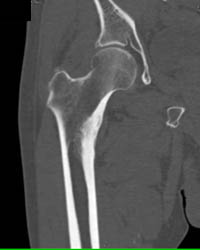

Sarcoma in Thigh With Necrosis